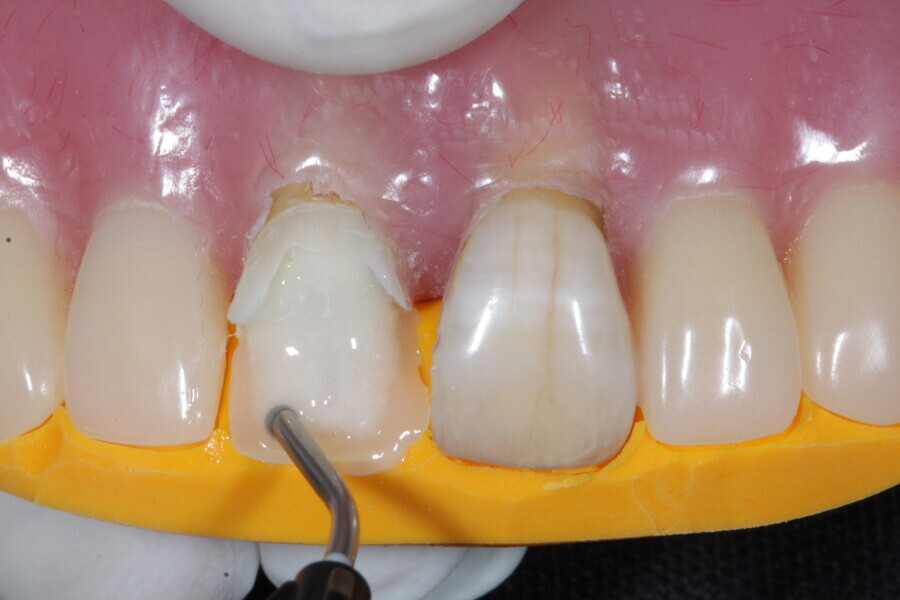

1. functional and aesthetic reconstruction of a maxillary anterior tooth using fibre-reinforced flexible micro-posts after endodontic treatment (Figs. 3–20);

Example 1—showing functional and aesthetic reconstruction of a maxillary anterior tooth using fibre-reinforced flexible micro-posts after endodontic treatment.

The second step focuses on reinforcing the restoration through careful fibre and FRC selection and placement. Tooth preparation should involve minimal removal of tooth structure to preserve as much natural tooth as possible in preparing the cavity for the restoration. Fibres or layers of FRC (flowable, paste, cube, etc.) are then strategically placed within the prepared tooth and composite material to reinforce areas susceptible to high stress and occlusal forces based on occlusal contact mapping. This strategic selection and placement of fibres and layers of FRC is crucial for enhancing the strength and longevity of the restoration.

The third step is to restore the tooth to its natural form, function and aesthetics. Composite resin, along with fibres or fibre-reinforced flowable or fibre-reinforced dentine substitute materials, is carefully applied to the prepared tooth structure. A layering technique is often used to ensure proper adhesion and integration of the reinforced materials with the composite material, enhancing the overall strength and functionality of the restoration. The composite resin is then polymerised using a curing light, ensuring that the materials are securely bonded within the restoration and providing a stable and long-lasting result. During this restorative process, the clinician should take special care not to expose fibres or FRC layers to the oral environment, as this can cause tissue irritation and water absorption by the materials in the long run. Therefore, the final layers of the restoration should always be a suitable aesthetic conventional composite resin.